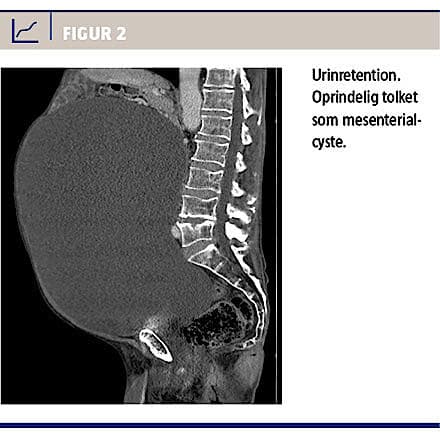

Endelig må det anbefales, at man ved fund af cystiske, abdominale processer altid overvejer urinretention som differentialdiagnose (Figur 2). Blæren kan være så stor, at man ikke kan få øje på den, og selv monstrøs retention kan forekomme uden større påvirkning af de øvre urinveje.

En 75-årig mand blev henvist til Urologisk Afdeling, Rigshospitalet, med venstresidig nyretumor. Patienten havde på grund af stigende abdominalomfang fået foretaget CT, hvor man dels fandt en tumor i venstre nyre, dels en stor mesenterialcyste. Ved revurdering af CT’en fandt man tillige en højresidig nyretumor. Der var ingen hydronefrose.